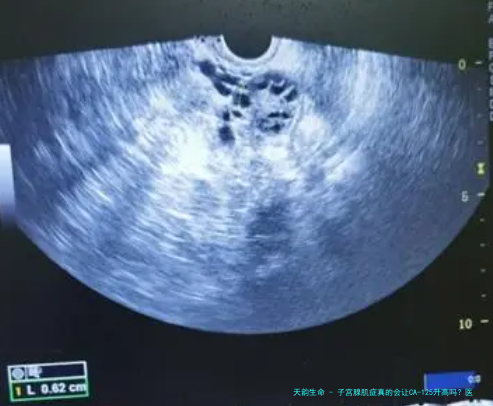

那么,子宫腺肌症到底会不会让CA-125升高呢?答案是:会的,而且概率不低。近年来的临床数据表明,大约30%-50%的子宫腺肌症患者CA-125水平会轻度到中度升高。这主要是因为腺肌症会导致子宫组织发炎和损伤,释放出CA-125进入血液。比如说,一项2021年的回顾性研究跟踪了500名腺肌症患者,发现其中40%的人CA-125值超过35 U/mL,但绝大多数都是良性升高,没发展到癌症。不过,这里得提醒一下,CA-125升高不是诊断腺肌症的金标准——它更像一个“提示信号”,需要结合B超或MRI来确认。另外,如果CA-125值异常高,比如超过100 U/mL,那就得警惕其他问题,比如卵巢肿瘤,但这种情况在腺肌症中相对少见。

来,我给大家讲个真实案例(基于常见情况虚构)。小张,一位35岁的职场妈妈,最近总感觉痛经越来越严重,月经量也大得让她贫血。她去体检时,CA-125测出来是48 U/mL,略高于正常值。一开始,她吓得够呛,以为得了卵巢癌。后来,医生给她做了盆腔超声,发现子宫壁增厚,有典型的“腺肌症表现”。经过进一步检查,确诊是子宫腺肌症,CA-125升高正是由这个病引起的。小张松了口气,开始接受药物治疗,CA-125值也逐渐回落。这个故事告诉我们,CA-125高不一定就是癌,可能是良性病在“作怪”。咱们得学会全面看问题,别光盯着一个数字。